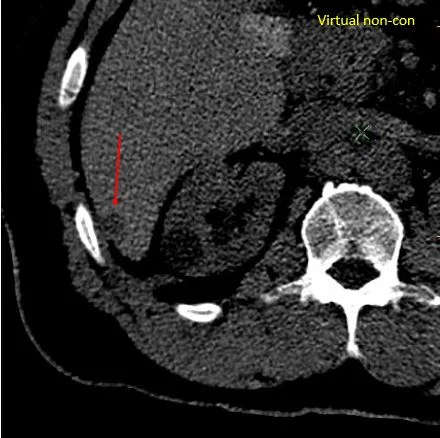

Virtual non-contrast: Lesion pops out again.